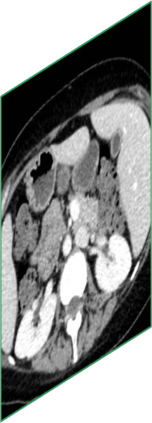

Due to the constraints of the imaging device and high cost in operation time, computer tomography (CT) scans are usually acquired with low intra-slice resolution. Improving the intra-slice resolution is beneficial to the disease diagnosis for both human experts and computer-aided systems. To this end, this paper builds a novel medical slice synthesis to increase the between-slice resolution. Considering that the ground-truth intermediate medical slices are always absent in clinical practice, we introduce the incremental cross-view mutual distillation strategy to accomplish this task in the self-supervised learning manner. Specifically, we model this problem from three different views: slice-wise interpolation from axial view and pixel-wise interpolation from coronal and sagittal views. Under this circumstance, the models learned from different views can distill valuable knowledge to guide the learning processes of each other. We can repeat this process to make the models synthesize intermediate slice data with increasing inter-slice resolution. To demonstrate the effectiveness of the proposed approach, we conduct comprehensive experiments on a large-scale CT dataset. Quantitative and qualitative comparison results show that our method outperforms state-of-the-art algorithms by clear margins.